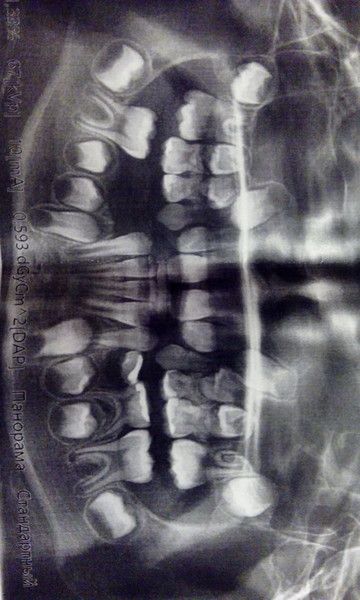

Наш врач говорит, что так сильно челюсть не вырастает. У моего тоже зубы крупные и мало места, два дня назад поставил аппарат несъемный (я за него и искала врача, который на этом специализируется). Будем расширять, сейчас в 8 лет самое время, все легко получится. Я в вашем снимке не очень понимаю, но у нас по нашему снимку несколько врачей сказали, что без расширения точно никак. Пластинки съемные сказали носить года два не меньше, аппарат марко-роса месяцев 6-8. А дальше брекетами выравнивать. Но должны вырасти единицы и шестерки для аппарата. А еще говорят, что аппарат ставят только наверх, а низ сам подтягивается и расширяется. Я бы еще где-то проконсультировалась. У нас вот так. Двойкам некуда расти. А дальше клыки и четверки..

Юлия-мама Жу-Жу, у нас такого нет. Чтобы на одно место по два зуба, зубы сами выпадают. По снимку видно расположение. Поэтому и сомневаюсь насчет аппарата.